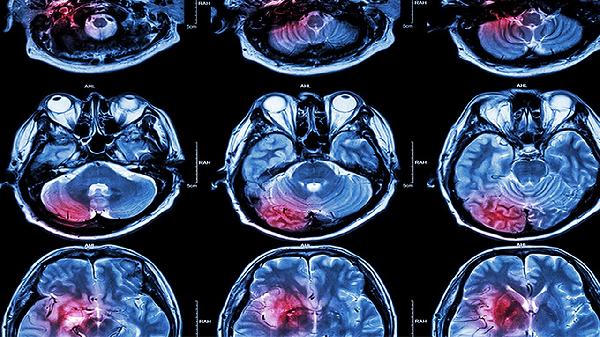

颅脑外伤导致的脑震荡是可以治好的,大多数人在接受及时的诊断和恰当的治疗后可以完全恢复。常见治疗方法包括充分休息、药物治疗以及必要的康复训练,具体方案需根据病情严重程度由医生决定。

脑震荡通常是由于外力撞击头部或颅脑外伤引起的,大脑可能在颅骨内受到震荡或短暂功能紊乱。症状包括头痛、恶心呕吐、短暂意识丧失、注意力难以集中或者记忆缺失等。轻度脑震荡常能在数周内自行恢复,但若症状持续或加重,如频繁头痛或昏迷,则需立即就医。